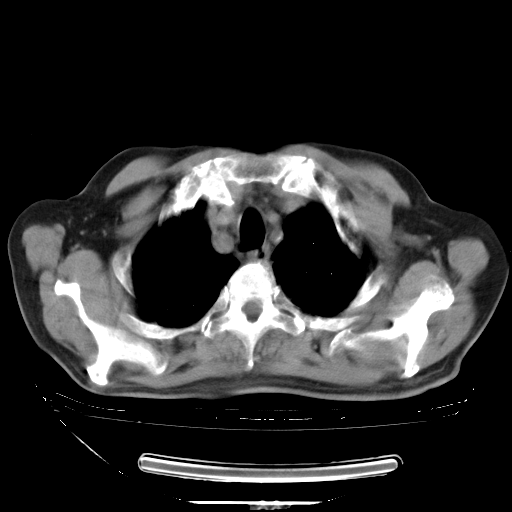

今天复查肺部CT,发现双肺广泛磨玻璃样改变。所以我把3月19日和5月9日相隔50天的肺部CT上传。请大家会诊。

2009年3月19日肺部CT片。

5月9日肺部CT(在4月27日齐鲁医院肺部CT描述部分肺组织磨玻璃样改变,12天后肺组织广泛磨玻璃样改变)

大致读了系列胸部CT:纵隔窗无明显异常,肺窗:从4、27至今:主要是双肺中下野外带可见毛玻璃样改变,目前处于急性肺泡炎阶段,至于原因考虑1、结替组织或胶原血管性疾病所致?2、恶性疾病如恶组在肺部所致的表现或细支气管肺泡癌?3、药物或其它原因如肺蛋白沉着症所致肺泡炎目前不太可能?总之,明天就去请我院的呼吸科、感染科、血液科和临免专家会诊哈。